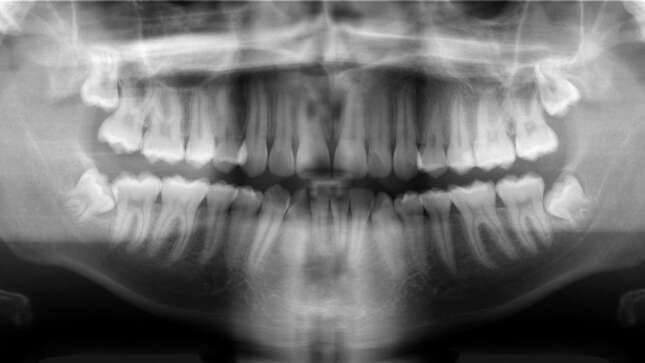

Al parecer, lo primero que hicieron los dentistas fue ordenar una radiografía y una tomografía computarizada. Esta, según P. Senthilnathan, profesor de cirugía oral y maxilofacial en Saveetha Dental College, reveló una “estructura en forma de bolsa” en la boca del niño que contenía 526 dientes. Una condición que se conoce como odontoma compuesto. Como explicó Senthilnathan al New India Express:

El crecimiento similar a un tumor impidió el crecimiento permanente de los molares del lado afectado. La radiografía y la tomografía computarizada mostraron múltiples dientes rudimentarios en un tejido similar a una bolsa.